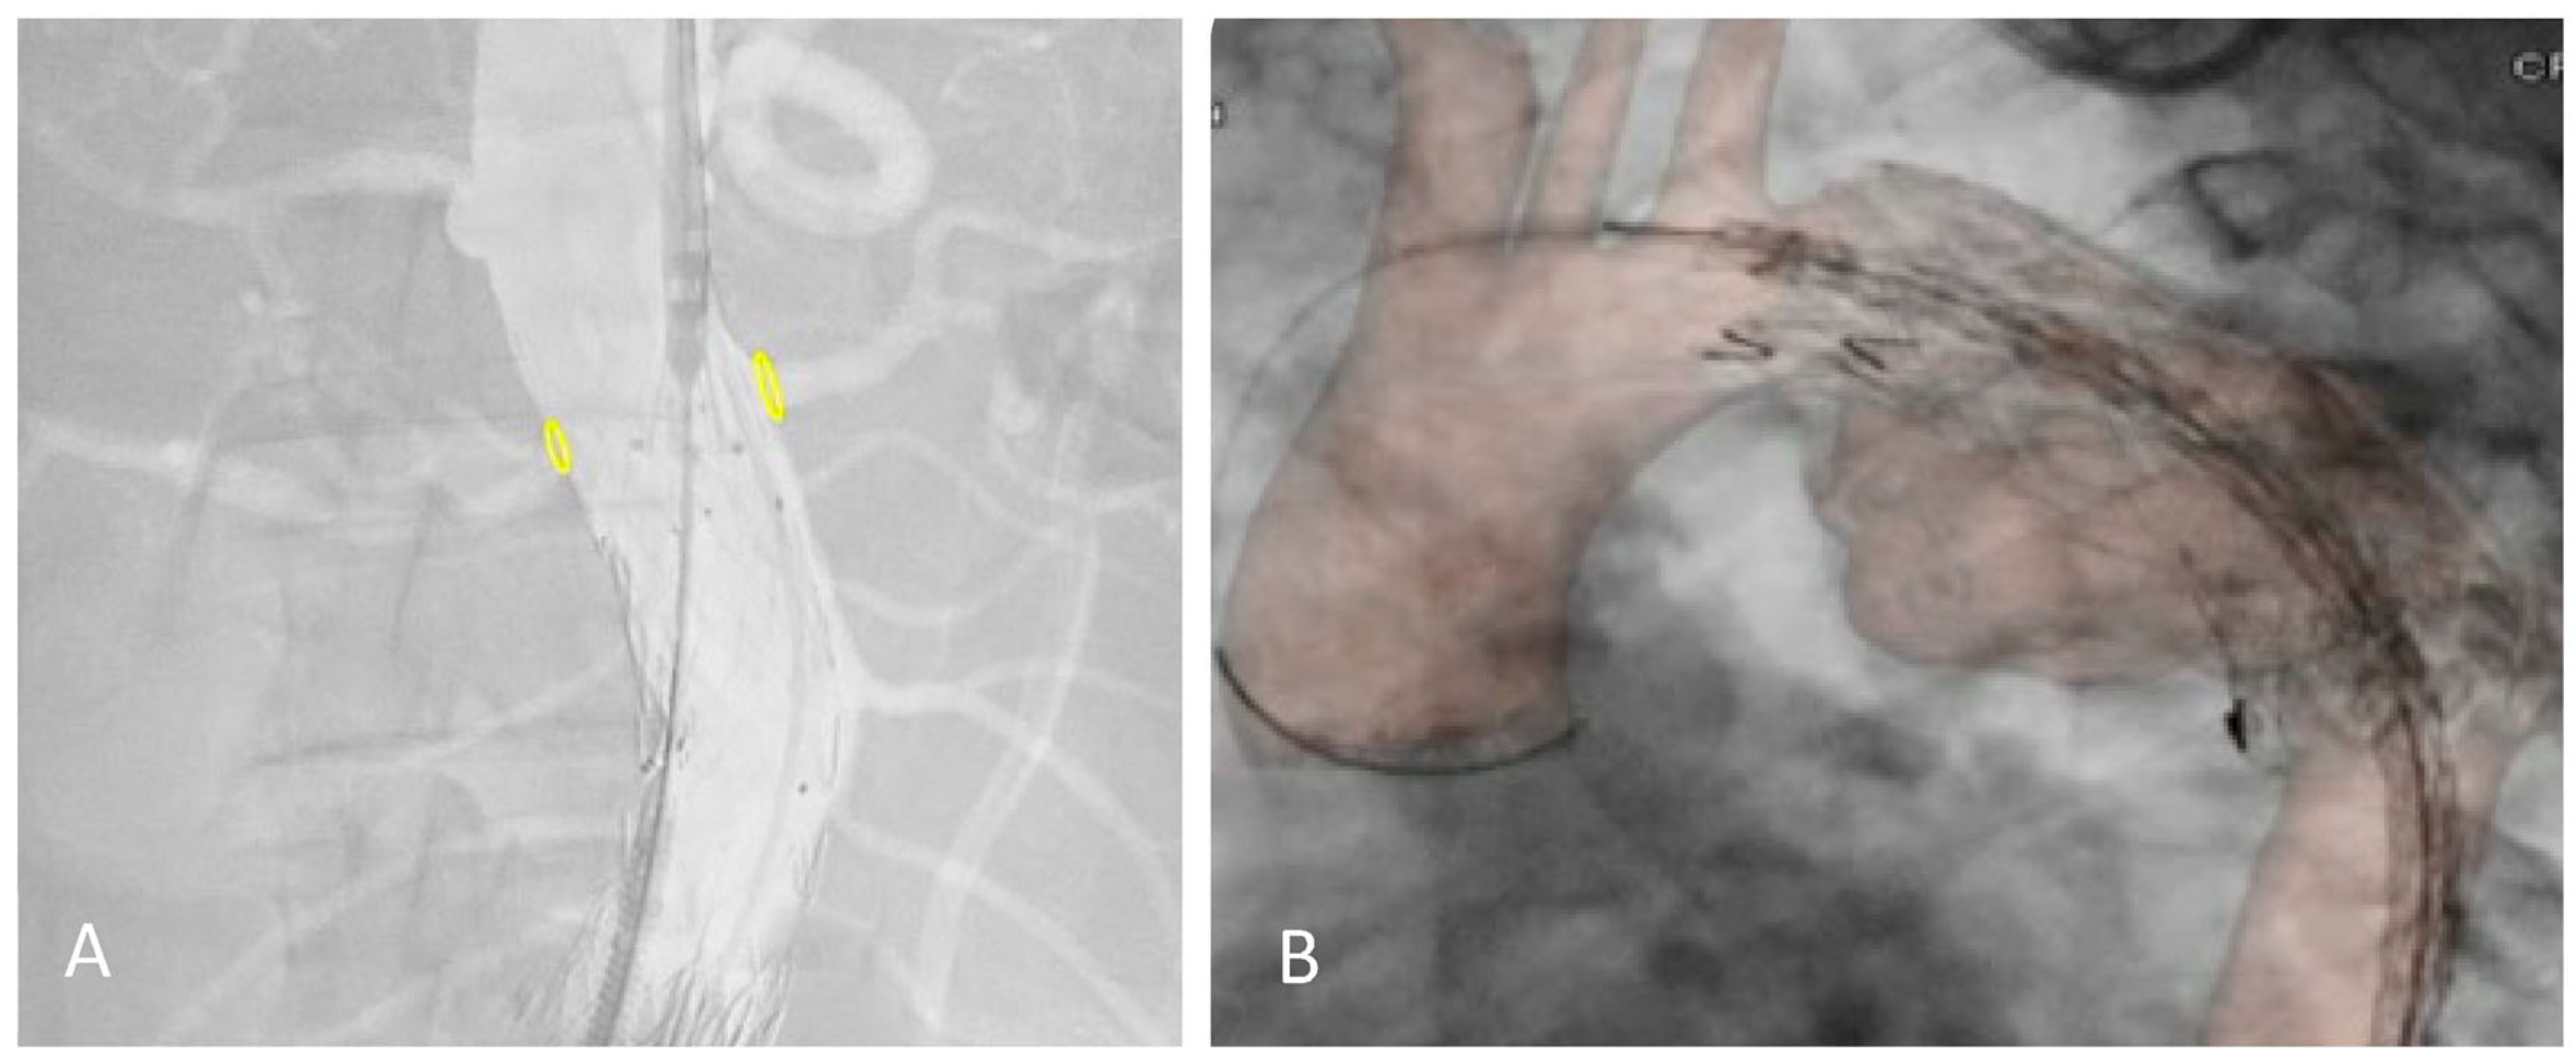

| Variables | Definition |

|---|---|

| P1 | Inferior margin of the target vessel ostium in digital subtraction angiography (DSA) |

| P2 | Inferior margin of the target vessel ostium in bone fusion |

| P3 | Inferior margin of the target vessel ostium in redo fusion |

| L1 | P1–P2 distance |

| L2 | P1–P3 distance |

| Working area | The new endovascular redo area containing the target vessel |

| Aortic angulation | Aortic angulation in the working area |

| Target vessel | The target vessel nearest the previous endovascular stent-graft |